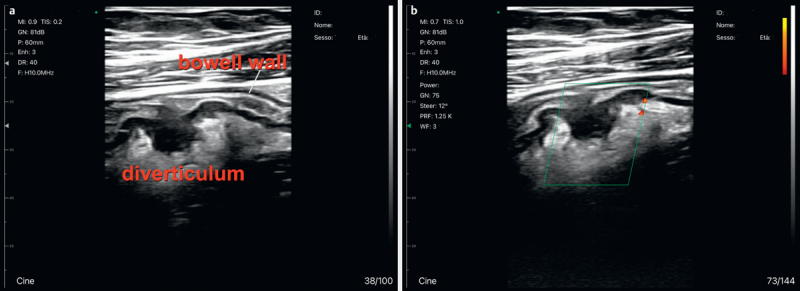

目的 手持式超声波(HH-US)可解答急诊中的简单临床问题。我们在就诊期间(MED)在病人床边(BED)用 HH-US 进行了传统超声检查(BED MED-US)。这项前瞻性研究的目的是评估 BED MED-US 的可靠性、其在帮助临床医生做出正确诊断方面的临床效果以及其节省时间和金钱的能力。材料和方法 在一个或多个地区对 1007 名患者(519 名男性;年龄:76.42 岁)进行了评估(从 2021 年 3 月到 2022 年 11 月)。通过临床和参考检查(胸部 RX/CT、腹部 CT、内窥镜检查等)确定最终诊断。对敏感性、特异性、LR+ 和 LR- 以及相应的 AUROC 进行了评估。HH-US 诊断分为:确诊(HH-US 发现的超声波征象证实了临床诊断)(CO)、排除(HH-US 在临床鉴别诊断中排除了其他病变的超声波征象)(EX)、病因诊断(HH-US 在临床可疑病例中得出诊断)(ET)或临床相关附带诊断(HH-US 诊断完全改变了患者的病程)(INC)。结果 HH-US 可靠性:true-pos:真阳性:752 例;真阴性:242 例;假阳性:7 例;假阴性:6 例:7; false-neg: 6 (sens: 99.1%, spec: 97.6%, LR+: 98.5; LR-: 00.15, AUROC: 0.997);临床影响:临床影响:CO-诊断:21%;EX:25%;ET:47%;INC:7%;节省的时间和金钱:约 35,572 分钟的工作时间和 9324 欧元。结论 BED MED-US 是一种可靠的临床成像系统,在诊断(47% 为病因诊断,7% 为偶然诊断)和人力资源管理方面都具有重要的临床影响。

Purpose Handheld ultrasound (HH-US) answers simple clinical questions in emergencies. We performed conventional US with HH-US at the patient's bedside (BED) during a medical visit (MED) (BED MED-US). The purpose of this prospective study is to estimate BED MED-US reliability, its clinical impact in helping the clinician to formulate correct diagnoses, and its ability to save time and money. Materials and Methods 1007 patients (519 M; age:76.42) were assessed (from March 2021 to November 2022) in one or more districts. Final diagnosis was determined with clinical and reference tests (chest RX/CT, abdominal CT, endoscopy, etc.). Sensitivity, specificity, LR+ and LR-, and corresponding AUROC were evaluated. HH-US diagnoses were classified as: confirmation (HH-US revealed the sonographic signs that confirmed the clinical diagnosis) (CO), exclusion (HH-US excluded the presence of the ultrasound signs of other pathologies, in the clinical differential diagnosis) (EX), etiological (HH-US reaches diagnosis in clinically doubtful cases) (ET), or clinically relevant incidental (HH-US diagnoses that change the patient's process completely) (INC). Results HH-US reliability: true-pos: 752; true-neg: 242; false-pos: 7; false-neg: 6 (sens: 99.1%, spec: 97.6%, LR+: 98.5; LR-: 00.15, AUROC: 0.997); clinical impact: CO-diagnosis: 21%; EX: 25%; ET: 47%; INC: 7%; saved time and money: approximately 35,572 minutes of work and 9324 euros. Conclusion BED MED-US is a reliable clinical imaging system, with an important clinical impact both in diagnosis (etiological in 47%, incidental in 7%) and in the management of personnel resources.